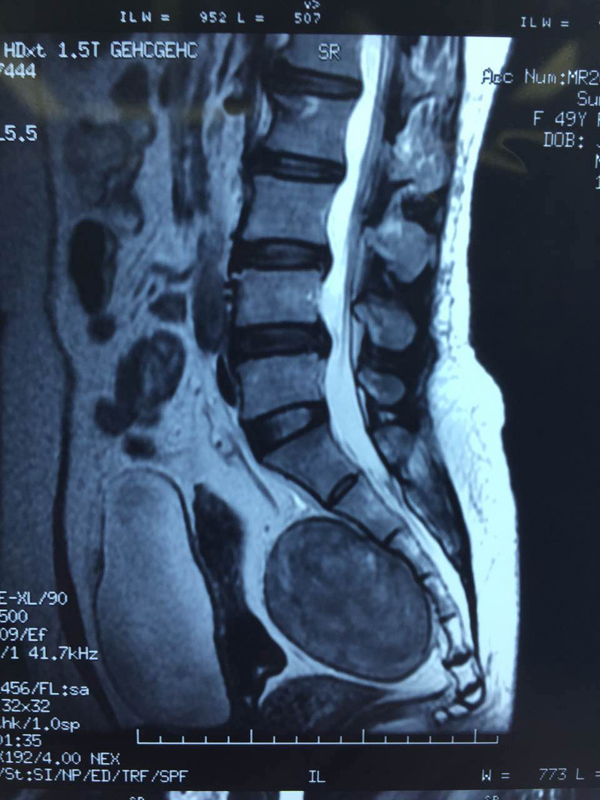

家住寿县的孙女士今年49岁,一年多来经常感觉小腹胀痛、腿麻木,尤其过完年后突然加重,有时疼得直不起腰来。家人带着孙女士来到安医一附院就诊,经过CT和磁共振检查,孙女士的盆腔内竟然有一个梨子大小的肿瘤。

肿瘤长在直肠后,位置很深,贴近骶前静脉丛,与神经根相连,周围大血管较多,手术难度大,很容易发生大出血,甚至危及生命。我院医务处联合普外科、妇产科、神经外科、脊柱外科、泌尿外科进行多学科会诊,经过严谨的讨论分析,最终由普外科专家进行手术。

曹先东介绍,孙女士的肿瘤属于神经源性肿瘤,不仅位置深,而且紧贴骶骨非常牢固,切除剥离的过程比较困难。肿瘤周围血管神经密布,稍有不慎会造成大出血或者伤及神经、影响下肢的正常活动。目前,孙女士恢复良好,没有出现任何并发症,一周之后就可以出院了。